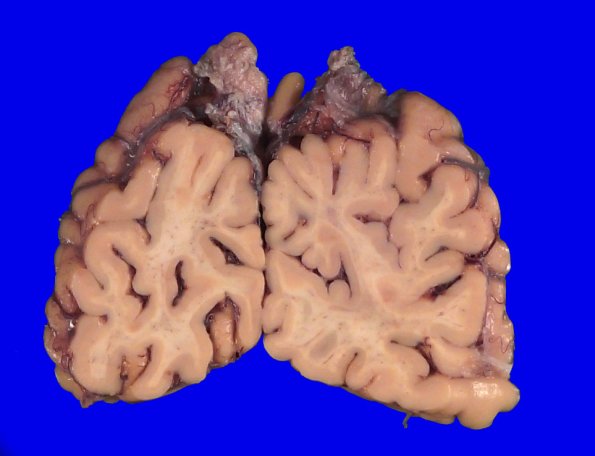

The cerebral cortex continues to show greater loss in the depths of sulci, particularly in the superior/middle frontal gyri. The lateral ventricles show global ventriculomegaly.